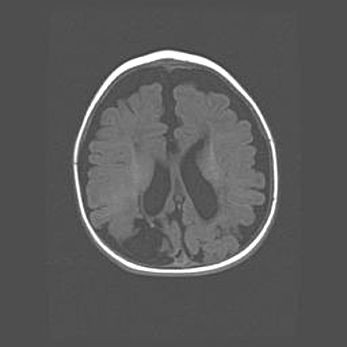

Открытая гидроцефалия.

Возраст: 9 месяцев 12 дней

Вес: 6800 г

Пол: мужской

Окружность головы: 41,5 см

Срок гестации: 28 недель

Гидроцефалия головного мозга у новорожденных имеет характерный признак: опережающий рост окружности головы приводит к визуально хорошо определяемой гидроцефальной форме сильно увеличенного в объёме черепа. Детские неврологи определяют следующие симптомы гидроцефалии у грудничков: выбухающий напряжённый родничок, частое запрокидывание головы, смещение глазных яблок к низу.